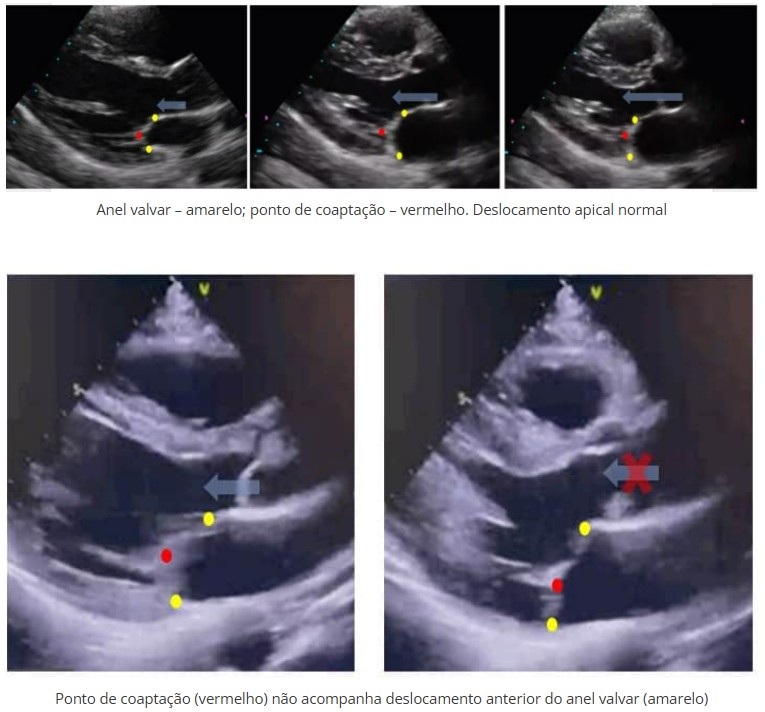

Definido como uma protrusão sistólica de um ou ambos os folhetos valvares ≥ 2 mm além do plano do anel valvar, na janela paraesternal ou apical, para o interior do átrio esquerdo (AE).

Com a evolução, a IMi pelo PVM pode causar sobrecarga volumétrica no ventrículo esquerdo (VE) e posterior remodelamento ao ponto que uma regurgitação secundária se estabeleça. O tethering associado a IMi funcional reduz o prolapso uma vez que limita o descolamento superior dos folhetos.